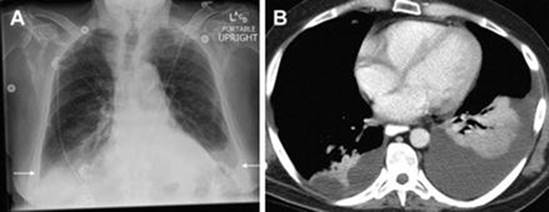

Pleural Effusion

In gynecology patients, pleural effusions will most commonly be identified in patients with ovarian hyperstimulation syndrome (OHSS) or malignancy. Pleural effusions are associated with a blunting of the costophrenic angles on chest radiograph (Fig. 15.2) [11]. A chest CT scan may be helpful in distinguishing pleural effusions from parenchymal disease or atelectasis [11]. An empyema (purulent pleural effusion) may be suspected when the pleura is thickened and enhanced around the pleural fluid.

Fig. 15.2

Pleural effusion . (a) AP chest radiograph shows blunting of the costophrenic angles and a small amount of fluid tracking up the pleural space laterally (arrows), indicating bilateral pleural effusions. (b) Axial CT image confirms moderate left and small right pleural effusions, with adjacent atelectasis (Reprinted from Bentz and Primack [11], with permission from Elsevier)